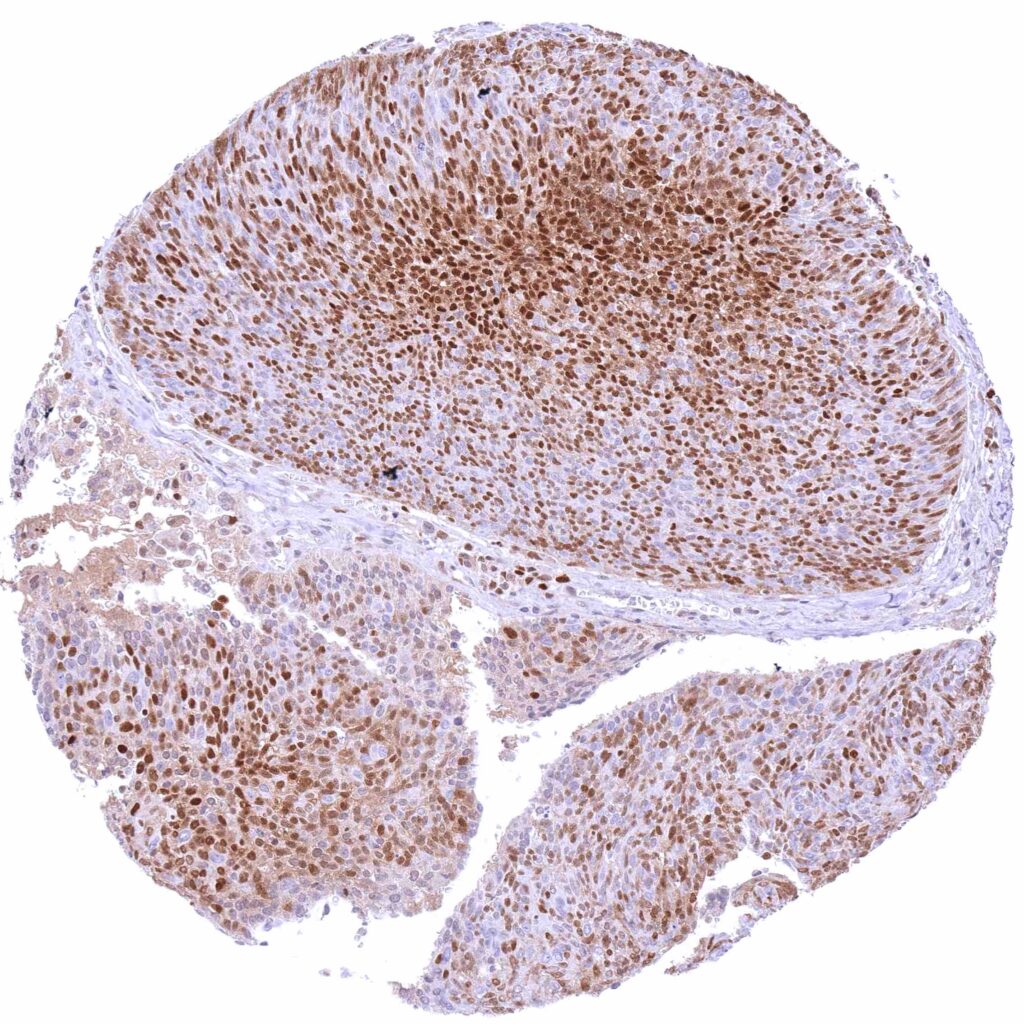

Pharynx – Squamous cell carcinoma with strong, predominantly nuclear p27 staining of most tumor cells.